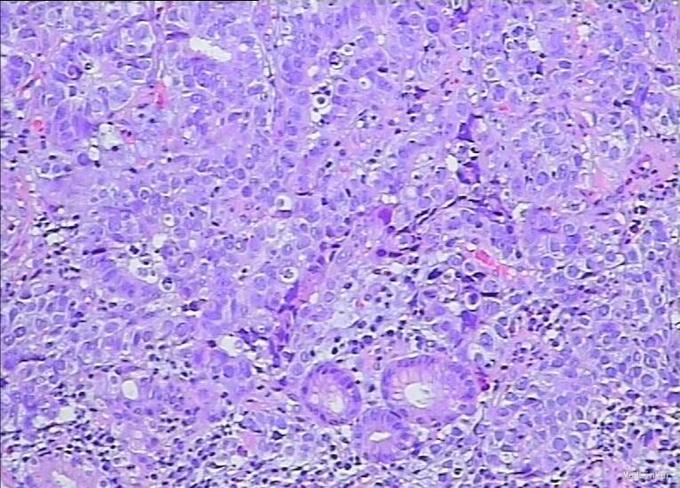

查体:无特殊。 辅查:腹增强CT:CT科室讨论:胃体部小弯侧胃壁弥漫性增厚,考虑胃癌并腹腔、腹膜后淋巴结转移可能性大,建议胃镜检查。 PET/CT提示:1.胃体小弯侧胃壁溃疡及胃周、肝门部及腹膜后多发肿大淋巴结糖代谢不同程度增高,考虑胃癌并多发淋巴结转移;其余部位未见恶性肿瘤代谢影像。 胃镜示:贲门、胃底、胃体:齿状线欠清,可见一巨大浸润肿物,从贲门延至胃底胃体,表面凹凸不平、溃烂,质脆触易出血,予活检。病理结果:(胃)分化差的癌,考虑为混合性腺神经内分泌癌。

诊断:胃 混合性腺神经内分泌癌 治疗:建议行IP方案化疗,但家属考虑后表示拒绝,经劝说无效。现予办理自动出院。